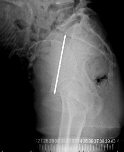

妊娠中に撮影する骨盤計測という撮影があります。妊娠中に放射線を浴びるのはいけないように思いますが、実際に使用する放射線量はごくわずかですし、この検査で帝王切開にするか自然分娩にするのか決定されますので非常に重要な撮影です。撮影されたX線写真で胎児の頭部の大きさと妊婦の骨盤の大きさを比べ、胎児の頭が大きければ帝王切開になります。大きさを計測しますので、メジャーを太ももの間に挟んで撮影することがあります。

右の写真では骨盤腔の入り口の大きさ(白線の産科真結合線)がエコー検査で調べた胎児の頭部より大きいので自然分娩可能です。